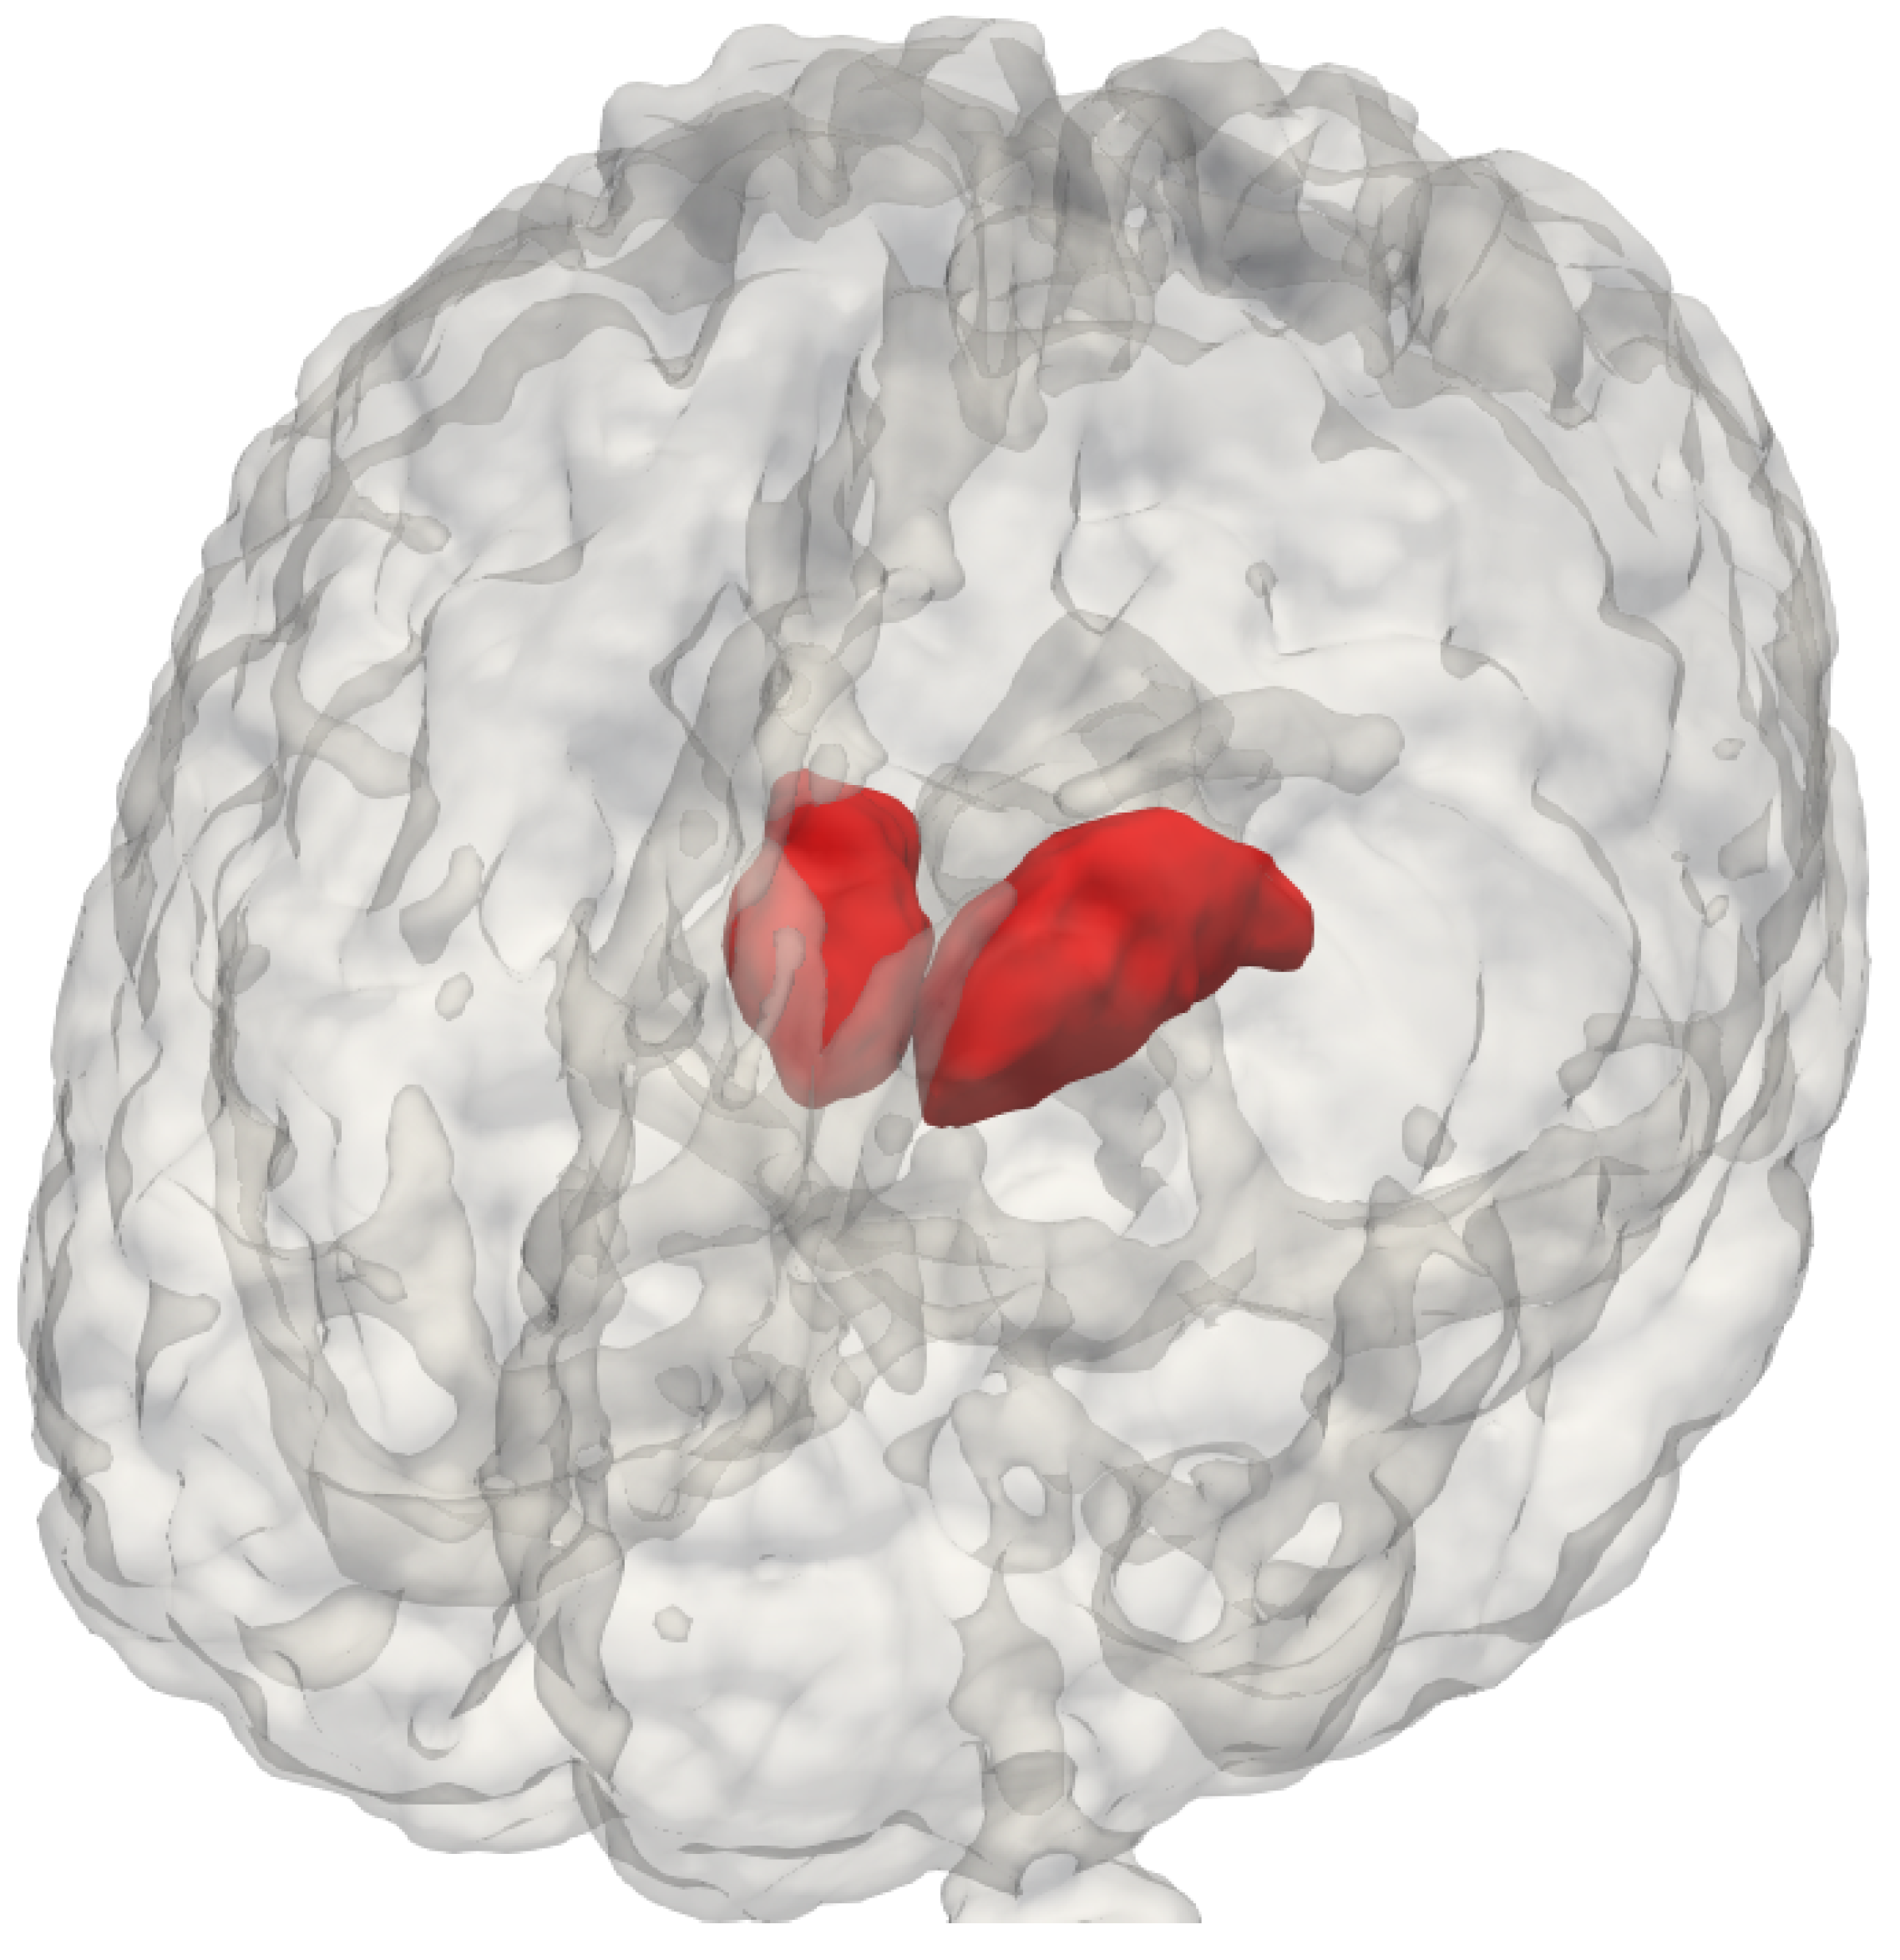

Figure 1.

The thalamus’s structure and location in the brain.